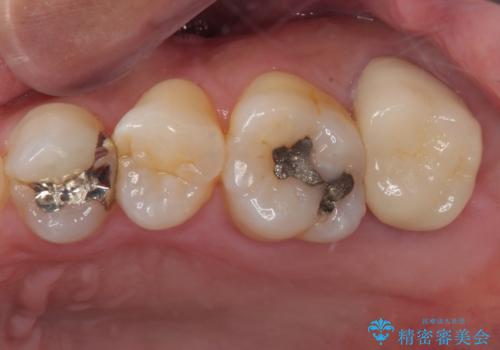

割れて揺れている奥歯 抜歯即時・早期埋入インプラント治療

抜歯とむし歯治療を途中で放置 インプラント補綴治療